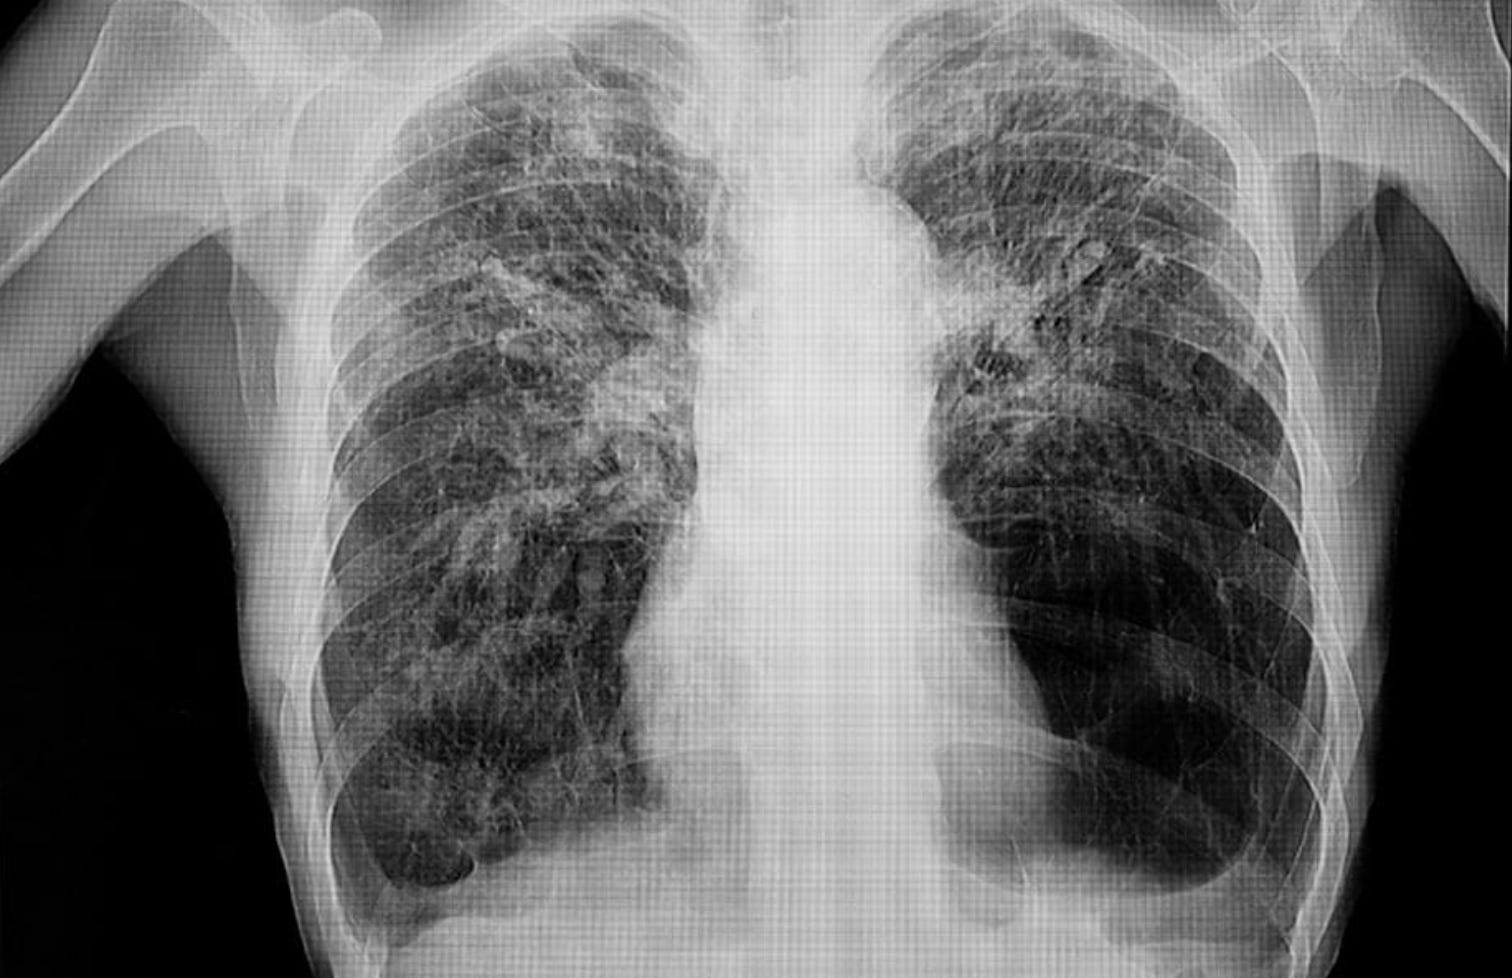

It is likely that these financial barriers contribute to the lack of Black and Hispanic enrollment in cancer clinical trials. According to a review of all Phase I oncology trials performed in the US and published in 2019, only 7% of patients are Black and less than 3% are Latino. For context, 15% of people with cancer are Black and 13% are Latino. This discrepancy in trial participation is in large part due to differences in enrollment rates. In 280 American cancer clinics from 2017-2022, only a little more than 4% of Black and Hispanic cancer patients enrolled in clinical trials compared to 7% of white patients. Unfortunately, this type of underrepresentation is the norm in clinical trials. Observing all US trials from 2000-2020, the majority report no ethnicity enrollment data at all. The studies that do report this data routinely underrepresent minority populations.